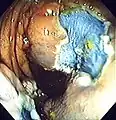

An advantage of colonoscopy over X-ray imaging or other less invasive tests is the ability to perform therapeutic interventions during the test. A polyp is a growth of excess of tissue that can develop into cancer. If a polyp is found, for example, it can be removed by one of several techniques. A snare device can be placed around a polyp for removal. Even if the polyp is flat on the surface it can often be removed. For example, the following shows a polyp removed in stages:

Polyp is identified.

Polyp is identified. A sterile solution is injected under the polyp to lift it away from deeper tissues.

A sterile solution is injected under the polyp to lift it away from deeper tissues. A portion of the polyp is now removed.

A portion of the polyp is now removed. The polyp is fully removed.

The polyp is fully removed.